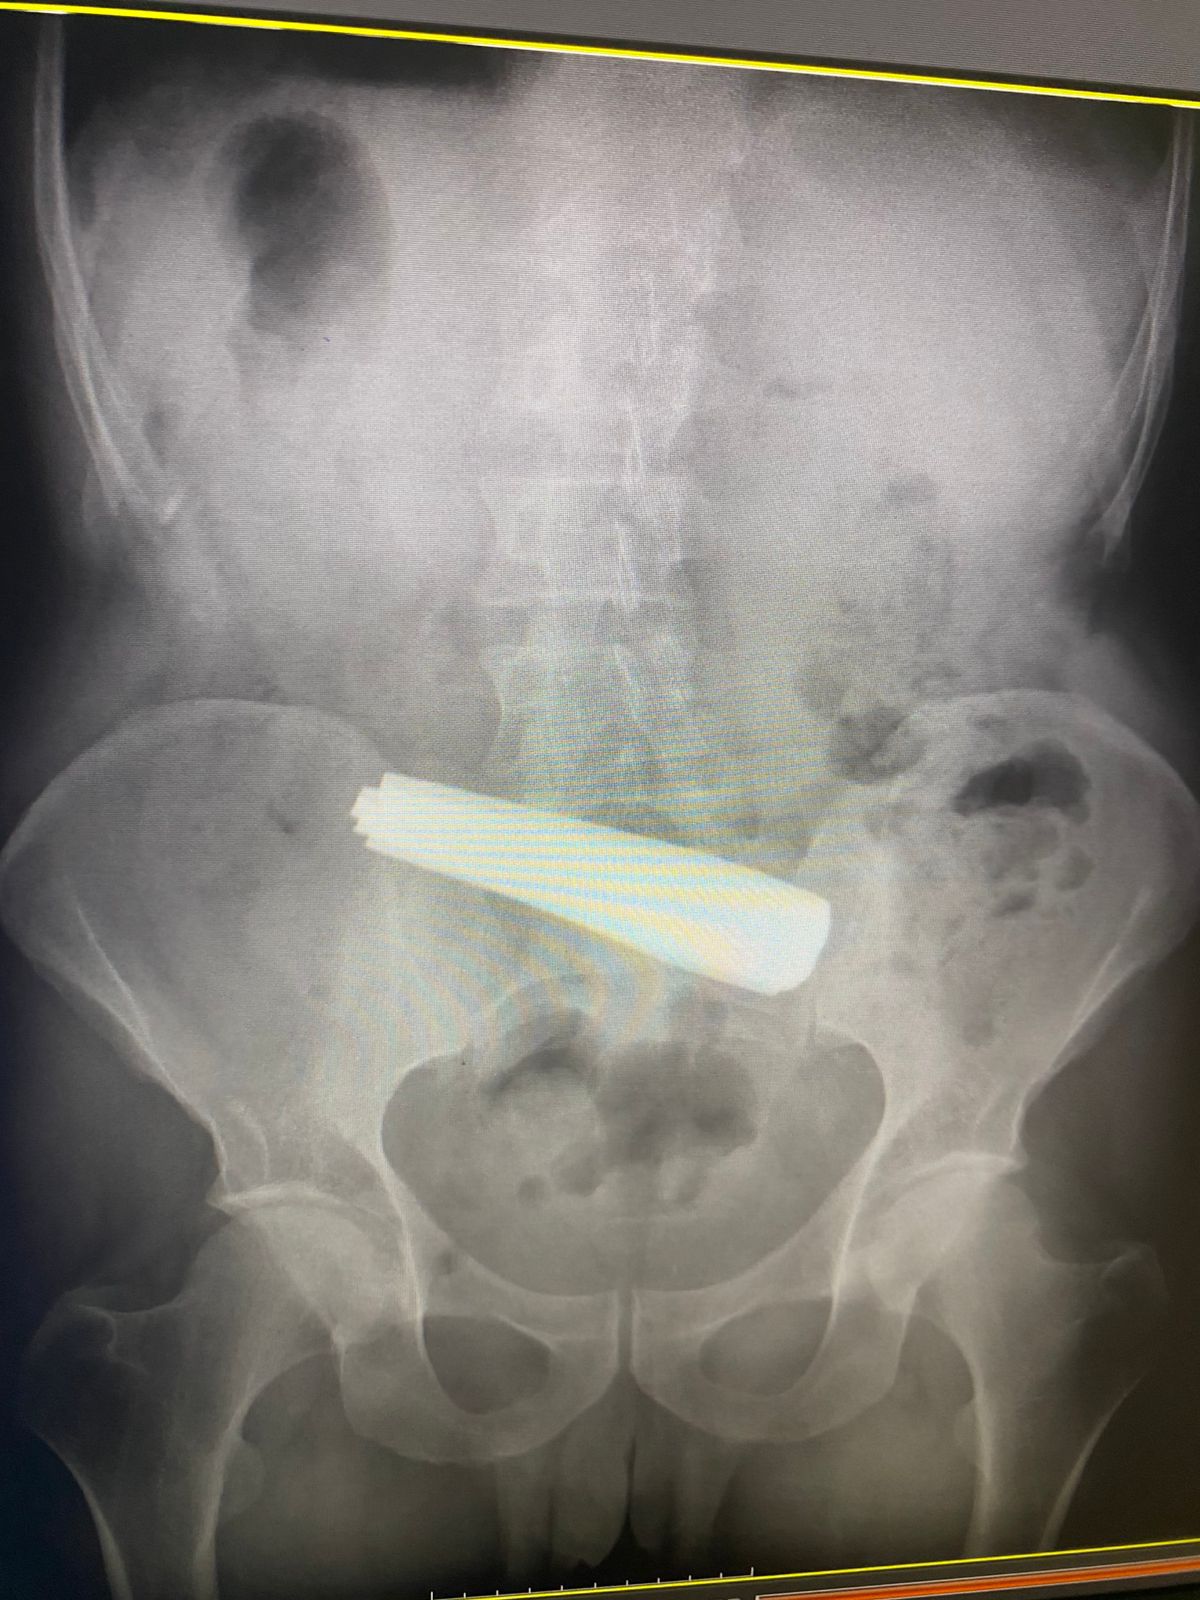

Bakıda 9 qaşıq udmuş kişinin həyatı xilas edilib.

"Endoskopik müdaxilə 4 saat davam edib və nəticə etibarilə zərərçəkənin vəziyyəti stabilləşdirilib.

Hazırda pasiyent reanimasiya şöbəsində müalicəsini davam etdirir, vəziyyəti stabildir".

Qeyd edək ki, 9 qaşıq udan xəstə 55 yaşlı kişidir. Pasiyentin bu hərəkətinin onun psixi vəziyyəti ilə əlaqədar olduğu ehtimal edilir.